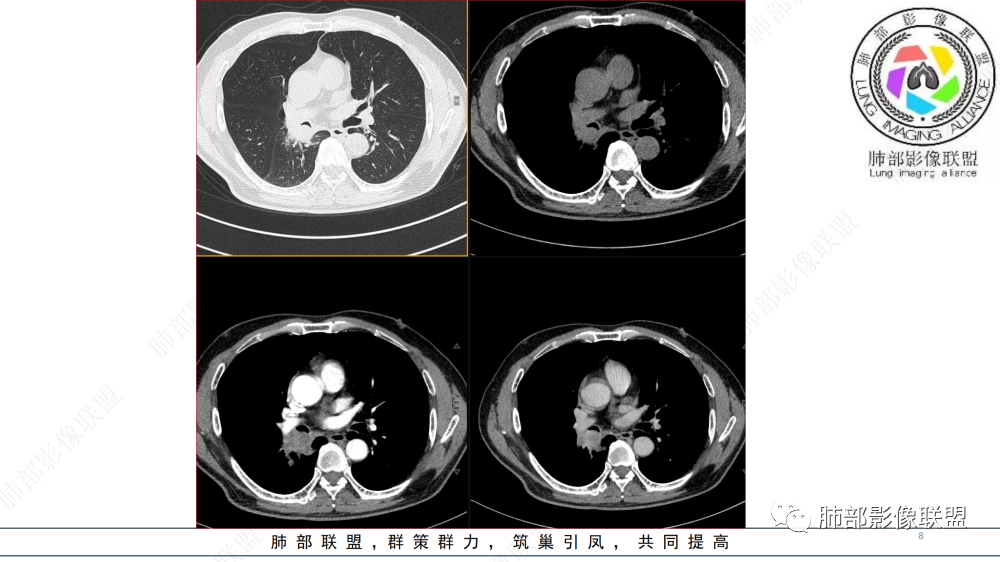

晨读 右肺中间段支气管至下叶支气管部分狭窄及堵塞,管壁偏侧增厚腔内外侵犯,软组织肿块形成,远侧肺内阻塞性炎症。考虑恶性病变,鳞癌,类癌可能

中年男性,咳嗽咳痰半年,有痰中带血,肿瘤标志物角蛋白稍高,右肺下叶支气管腔内肿块,支气管截断,有强化,考虑肺癌,鳞癌可能,鉴别类癌,粘液表皮癌等。

中年男性,痰中带血,病史半年,一直没有发热,感染指标不高,胸部CT右侧肺门不规则肿块影,边缘清楚,棘状突起,浅分叶,血管集支束,空泡征,不均匀强化,右肺斜裂结节状增厚,右侧中间支气管外压改变,右肺下叶背段支气管截断,无明显淋巴结肿大,恶性是没有问题,至于类型病灶大无坏死空洞,鳞癌靠后,无明显淋巴结肿大,小细胞靠后,所以腺癌首选。

晨读:男,57岁,咳嗽咳痰半年,右肺下叶支气管腔内肿块影,管壁增厚,管腔狭窄,增强扫描呈不均匀性强化,考虑恶性病变,鳞癌可能。

晨读病例,中年男性,咳嗽咳痰半年,有痰中带血,影像表现右肺下叶支气管腔内外占位,形态欠规则,有冰山征表现,支气管截断,有强化,考虑恶性病变,类癌或鳞癌可能,鉴别腺癌、粘液表皮癌等。

右肺下叶肺门区肿块,向中间段支气管突出,下叶支气管阻塞狭窄,腔内外侵犯,不均匀强化,内可见低密度,冠状位病变沿支气管走行生长,远侧肺内阻塞性炎症,考虑鳞癌,鉴别类癌

中老年男性,右肺下叶背段支气管内新生物,近端可见息肉样突起,远端沿分支支气管生长堵塞,肺门口病灶增强后明显强化,峰值达140hu,远端部分强化不明显考虑粘液栓,考虑典型类癌,鉴别鳞癌。

右肺下叶背段支气管腔内占位伴周围肿块支气管截断,有强化,考虑恶性病变,类癌可能,鉴别腺癌。

右肺叶中间段支气管见软组织影不完全阻塞及管腔变窄,向管腔外突破,向下叶背段浸润性生长,见指套及息肉样特点,不均匀明显强化,右肺下叶背段少许阻塞性炎症,肯定恶性肿瘤,小细胞Ca首先,支气管疾病谱恶性肿瘤:类癌,鳞癌,囊腺癌,粘液表皮样癌,与鳞癌,囊腺癌鉴别,支气管镜取材活检可以明确诊断。

晨读,右肺中间段及下叶支气管管腔占位,向管腔内突入,浸润性生长,支气管近端截断,周围少许阻塞性炎症,增强后轻度强化,考虑类癌,腺样囊性癌

右支气管腔沿管壁占位,病灶不彻底的坏死是不均一强化,胆碱脂酶异常升高,首选鳞癌!鉴别类癌

右肺中间段及下叶支气管腔内外生长肿块,远端未见明显阻塞改变,不均匀渐进强化,考虑腺样囊性癌或类癌

晨读:男,57,咳嗽半年,痰中带血3天。胸部CT:右中间段支气管到下叶支气管堵塞性狭窄,管腔内见软组织肿块,壁内外侵犯,长轴沿气道延展,下叶基底多段累及,病变纵径大于横径,远侧可见索条、阻塞性炎症。考虑恶性,腺样囊腺癌?鳞?鉴别N内分泌类、炎性肉芽肿等

右肺支气管部分狭窄及堵塞,周围肿块,远侧阻塞性炎症。恶性病变,类癌,鳞癌,腺样囊性癌。

气管截断,血管破坏,跨壁内外生长,阻塞性炎症,定性恶性,明显强化,首先考虑类癌,鉴别鳞癌

中年男性,病史半年,不发热,有咳血,右肺门不规则肿块,向支气管内突出,不均匀强化,局部强化明显,远端有小尾巴,考虑恶性肿瘤,类癌、小细胞、鳞癌。